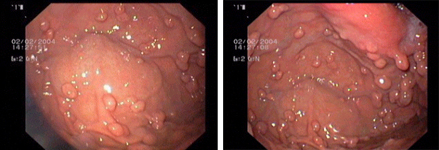

Endoscopic images:

imagen1

Endoscopic image of a flat polyp in the colon, before (left) and after resection.